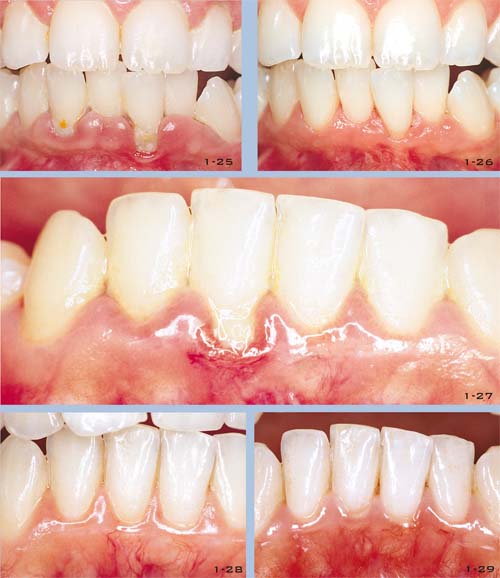

Danach erfolgt die ästhetische Analyse: Form und Größe der natürlichen Zähne oder Kronen, die ersetzt werden sollen, Relation der Zähne zum Weichgewebe und dem Gingivaverlauf, Tiefbisssituation, Kreuzbiss, Diastemata und die Beziehung der Zähne zu den perioralen Geweben. Diese Untersuchung kann die Notwendigkeit für eine präprothetische kieferorthopädische oder parodontale Vorbehandlung ergeben. Dies muss mit dem Zahnarzt diskutiert werden (Abb. 1-35 bis 1-42)11,12. Diese ästhetischen Prüfungen können die ideale Position der Zähne, die durch eine kieferorthopädische Behandlung erreicht werden kann, feststellen oder auch die Notwendigkeit, die Zahnrelation zum Weichgewebe durch mukogingival-chirurgische Maßnahmen zur Abdeckung von Defekten zu optimieren13,14.

Abb. 1-32 bis 1-33 Mit einer Feldspat-keramikkrone restaurierter Einzelzahn. Form- und Farbcharakteristika des kontralateralen Zahnes werden ohne kreative Spielereien kopiert. Abbildung 1-32 zeigt die klinische Situation vor Entfernung der alten Metallkeramikkrone. Abb. 1-34 Fotografien vom Lächeln des Patienten drücken oft Aspekte der Persönlichkeit und der Erwartungshaltung des Patienten aus. Abb. 1-35 bis 1-42 Das diagnostisches Aufwachsen entwickelt den Laborbehandlungsplan. Nur durch die Information über die restlichen Zähne und die Modelle im Artikulator kann der Techniker die definitive Krone aufwachsen. Die Art der geplanten Behandlung beeinflusst ebenso das Design der aufgewachsten Krone. Vor dem Herstellen der definitiven Krone wird eine provisorische Krone angefertigt, um ungünstige Parameter und Zahnstellungen modifizieren zu können und dadurch eine optimale Form und Funktion wieder herzustellen. In diesem Fall sind orthodontische Zahnbewegungen geplant, was manchmal auch eine Veränderung der Spee Kurve bedeuten kann. Die Abbildungen zeigen den Ausgangsbefund im Vergleich zum Wax-up der verschiedenen Segmente.